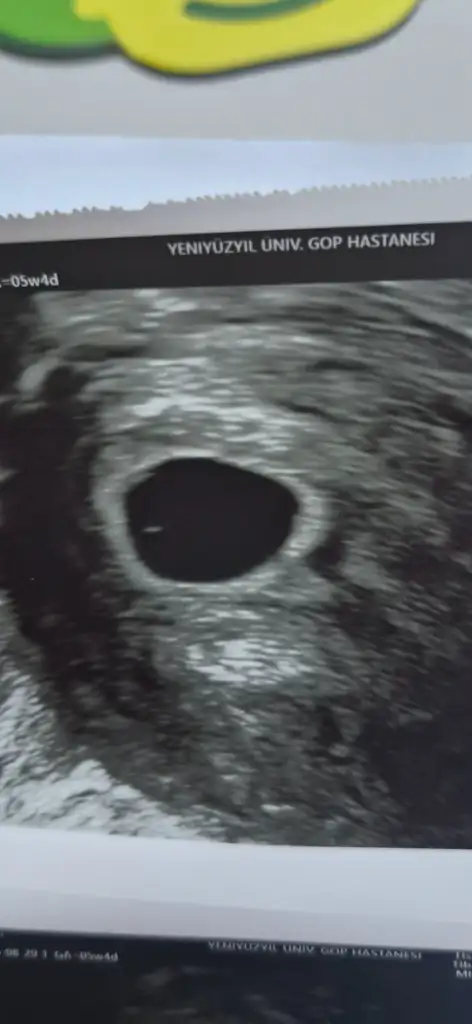

Merhaba teyzoşlarrrr.... 5+4 günlükmüşüm normal adetimden 4 gün ileri attı 3.gün embriyosu olduğu için sanırım. Şimdilik yolunda herşey bir hafta on güne kalp duyulur dedi.inşallahhhh 🤲🤲🤲 Artık kadındoğuma gidebilirsin dedi vedalaştık.🥲 30 eylüle kadar progesterona devam. Hamilelik boyunca da folikasit d vitamin coraspin devam dedi... Rabbim bütün kızkardeşlerime yaşatsın bu hissi 🐣😍